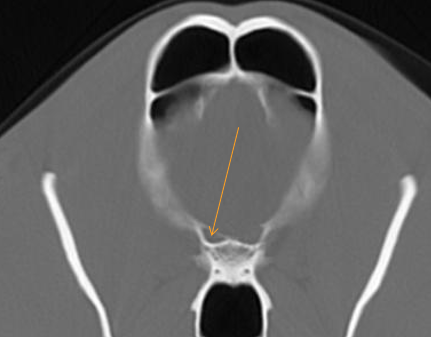

A round foramen, alar canal